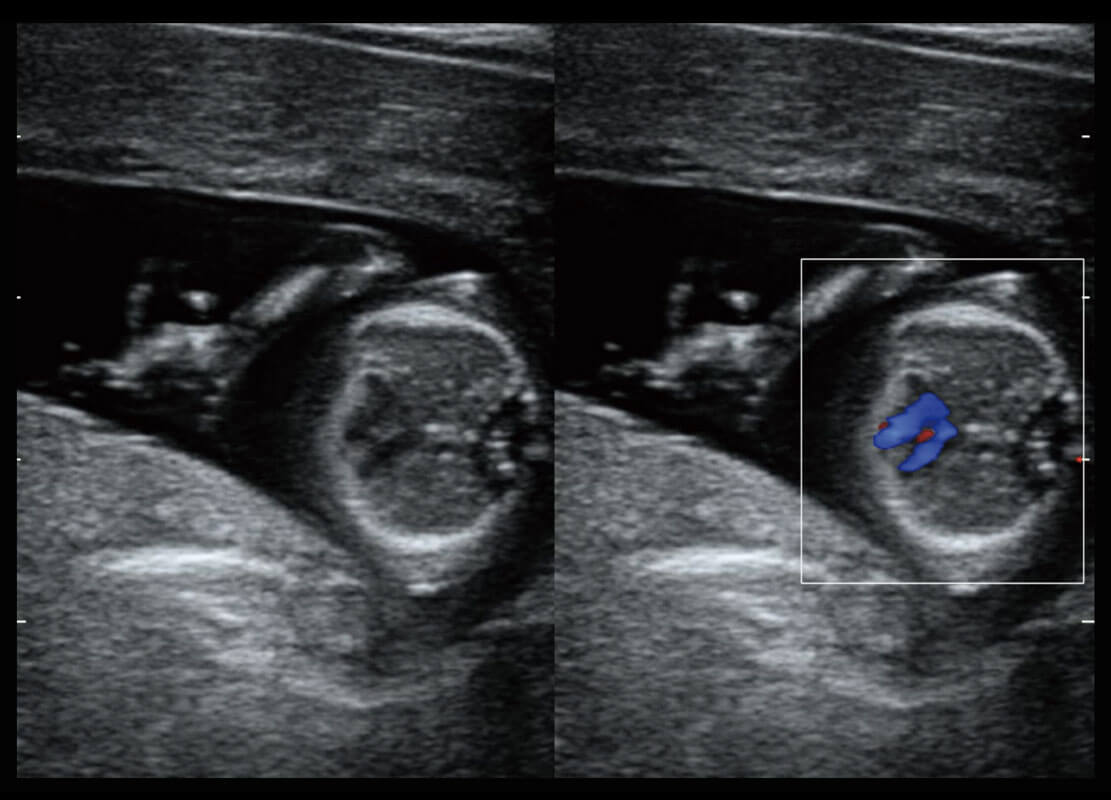

P60在胎儿早孕期超声筛查中为您带来优异的图像质量。

早孕-胎心

P60搭载一系列胎儿心脏成像技术,实现精细的胎儿心脏评估。

四腔切面

四腔心血流